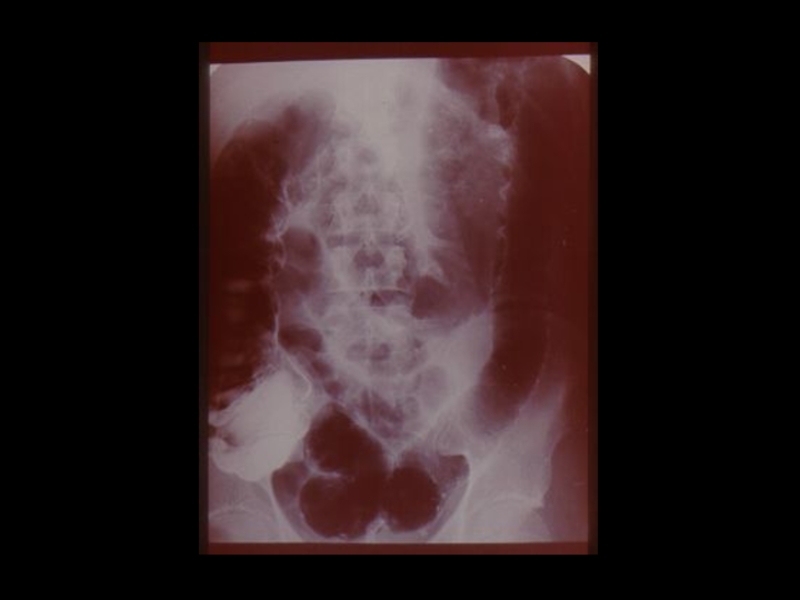

Слайд 18Методы традиционной рентгенодиагностики:

1. Общие методы

(рентгеноскопия, рентгенография)

2. Частные

методы

(флюорография, томография,

электрорентгенография, маммография и

другие)

3. Специальные методы

(урография, бронхография, ангиография,

лимфография, пневмоартрография и другие)

Методы традиционной рентгенодиагностики:1. Общие методы   (рентгеноскопия, рентгенография)2. Частные методы   (флюорография, томография,